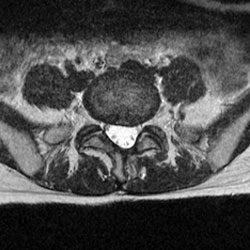

術後

ヘルニアはなくなっています。わずかな骨切除で手術可能です。

MRI

MRI